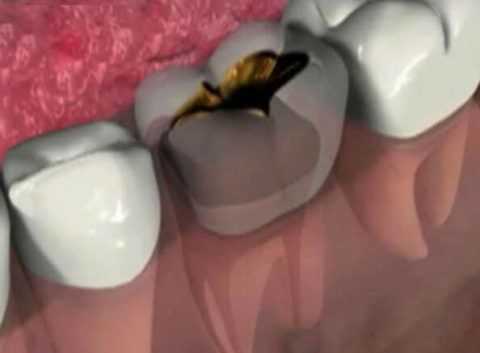

В зависимости от пути, которым микробы проникают в кость, различают эндогенный (гематогенный) и экзогенный остеомиелит. При гематогенном остеомиелите возбудители гнойной инфекции заносятся через кровь из удаленного очага (фурункул, панариций, абсцесс, флегмона, инфицированная рана или ссадина, тонзиллит, синусит, кариозные зубы и пр.). При экзогенном остеомиелите инфекция проникает в кость при ранении, операции или распространяется с окружающих органов и мягких тканей.

Источник инфицирования кости - это бактерии околозубных тканей, радикулярные кисты и опухолеподобные процессы челюстей. Самой распространенной причиной остеомиелита является периодонтит больших коренных зубов.

Достаточно одного невылеченного кариозного зуба, чтобы патогенный микроорганизм проник к тканям челюсти, а в результате произошло нарушение микроциркуляции и частичное отмирание клеток.

- запущенный кариес, пульпит и периодонтит с проникновением инфекции вглубь зуба.